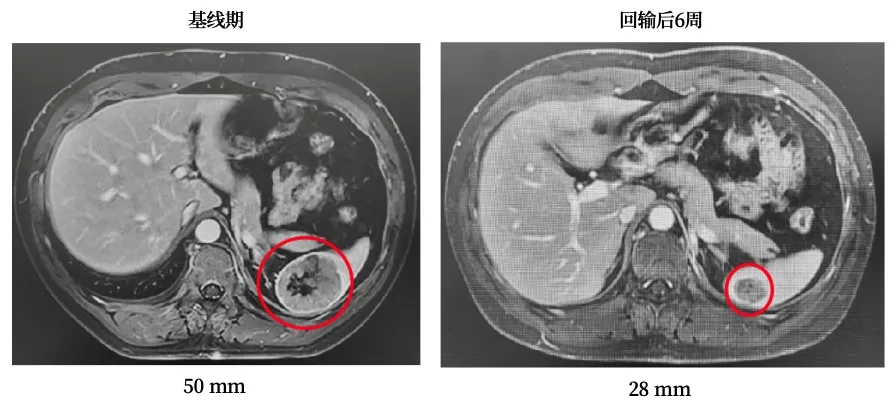

一名晚期肺腺癌患者合并淋巴结、胸膜及骨转移,放疗联合靶向治疗后病情仍进展,入组接受GC101细胞回输治疗。疗效评估结果振奋人心:回输后第6、12、18、24周影像学检查显示疗效递进显现,第二次增强CT即见靶病灶缩小36%(详见下图),最终达到部分缓解(PR);更惊喜的是,患者在回输后24周内未接受任何其他治疗,肿瘤病灶仍持续缩小,充分印证了GC101持久的抗癌活性。

▲图源“JUNCELL”,版权归原作者所有,如无意中侵犯了知识产权,请联系我们删除